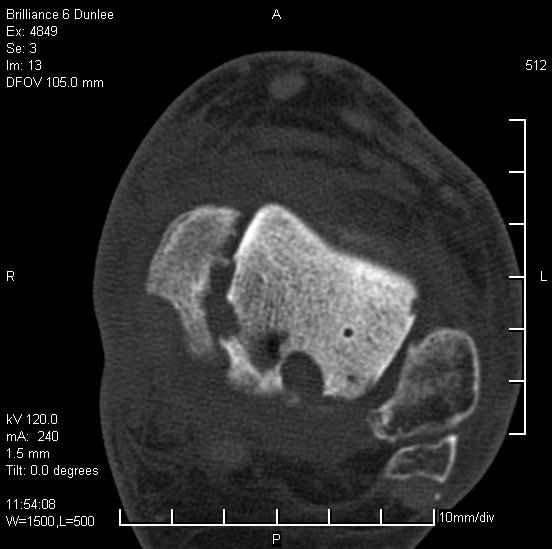

На лечении находится пациент 35 лет. Травма в сентябре 2008 г.- открытый вывих таранной кости

В день травмы ПХО, вправление вывиха, трансартикулярная фиксация. Рана зажила первично. С января нагрузка на конечность. С конца апреля- болевой синдром. На рентгенограммах и КТ признаки ас. некроза таранной кости, артроз подтаранного и голеностопного суставов.